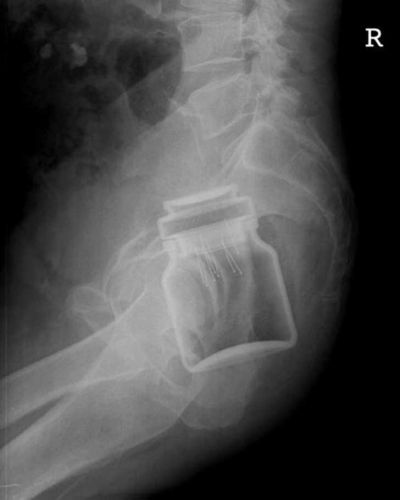

Tampa de embalagem de café solúvel